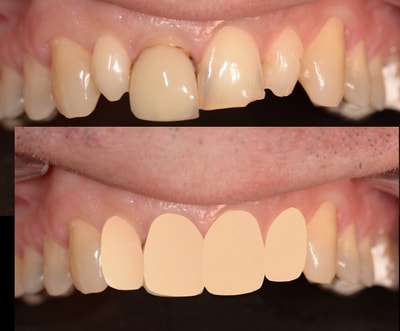

Cas numero 1 :

Situation Initiale

Etude du cas et proposition

Cas terminé

Cas numero 2 :